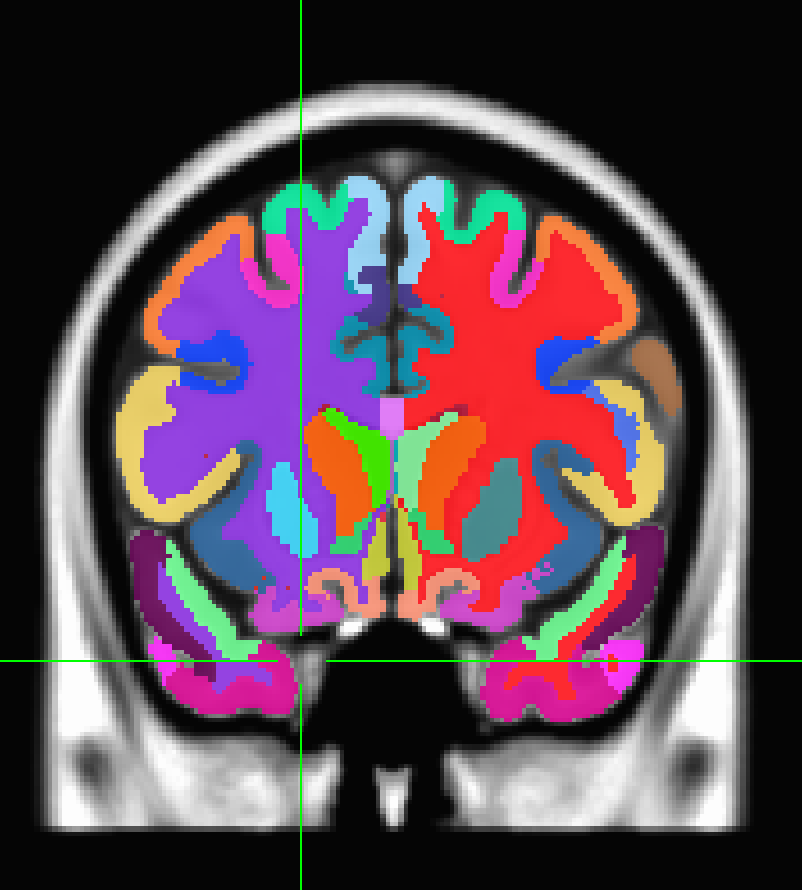

I have a segmentation NIfTI file (aparc+aseg+vep.nii) and a LUT file (VEP_atlas_AFNI.lt) that mimics the AFNI .lt format as follows,

the parcel names are displayed correctly, but the there are only two colors shown, one for grey and the other for white matter.

I placed the segmentation file and the corresponding nimal.cmap file (with the same name) in the same folder, but the colors in AFNI did not update. Is there a way to make the AFNI GUI automatically display the LUT colors?